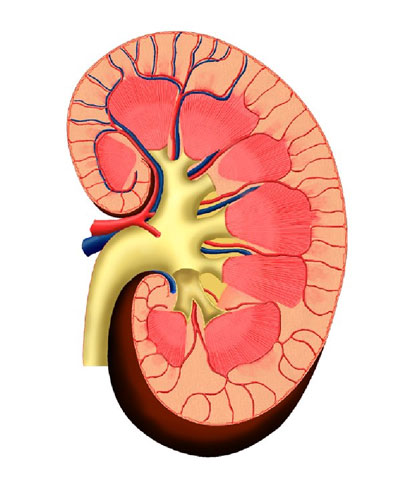

Строение почек человека: Фото и описание